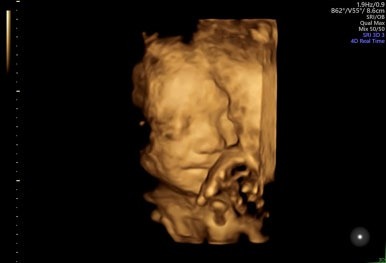

28주 1일

입체초음파로 태아의 얼굴을 볼 수 있는 시기이다!

제일 기다렸던 때이고, 다행히 태아 얼굴을 볼 수 있었다.